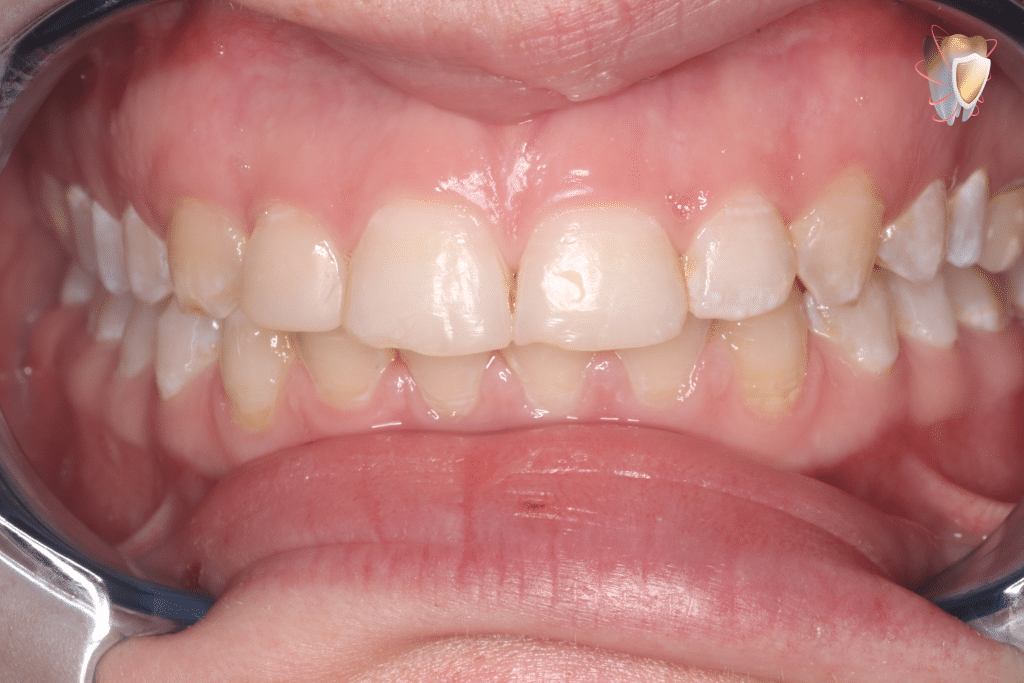

Social relaxed smile showing its extent from left 2nd premolar to right 2nd premolar

Distance from free gingival margin of left central incisor to lower border of the upper lip = 4mm

"note that 3mm or more is considered (gummy)"

Intra oral photo showing altered passive eruption & disharmony of gingival margins with each other